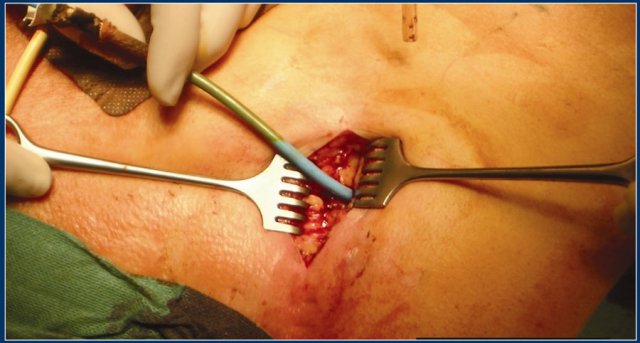

In this patient there is normal enhancement of the pancreas with surrounding septated heterogeneous acute necrotic collections with fluid- and fat densities.

This is probably necrosis of the peripancreatic tissues.

Two weeks later there are gas bubbles in the peripancreatic collection consistent with an infected acute necrotic collection.

This patient underwent surgery.

The surgeon removed a large amount of necrotic tissue and estimated he had removed over 90% of the pancreas.

Continue with the next image.

Remarkably, a CT performed 6 months after surgery showed a normal pancreas.

This indicates that during surgery the differentiation between pancreatic necrosis and necrosis of the peripancreatic tissues is sometimes impossible.